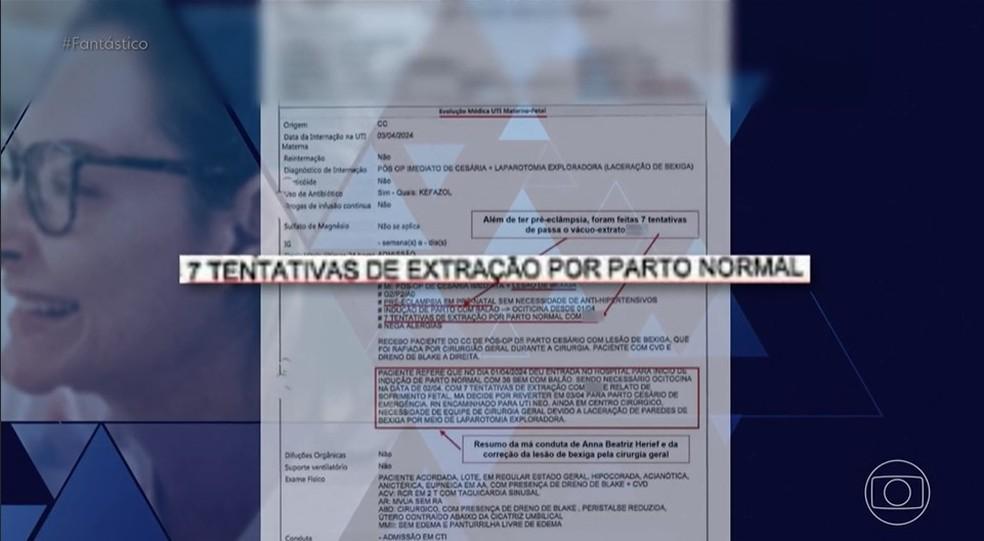

As denúncias vieram à tona através da reportagem do programa “Fantástico”. Segundo as pacientes, em vez de proporcionar um ambiente acolhedor e seguro, a médica teria realizado intervenções sem o consentimento das mães. A paciente Isadora Bueloni, por exemplo, relatou que “a médica usou um hormônio para intensificar as contrações uterinas sem meu consentimento”. Esse tipo de procedimento, quando realizado sem autorização, é considerado uma violação dos direitos da mulher durante o processo de parto.

Outro relato impactante foi o de Bianca Angelim, que afirmou que seu filho “nasceu morto” após complicações durante um parto supostamente induzido de forma inadequada. “Custou a vida do meu filho”, disse Bianca, explicando como foi orientada a mentir sobre sua condição de saúde para não ser encaminhada à UTI.

O obstetra perito Ivo Costa Júnior, que analisa um dos casos, destacou a “falta de comunicação” e os indícios de “negligência e imprudência” por parte da equipe da médica. Pacientes como Roberta Mendes também relataram sérios problemas que enfrentaram, incluindo dores persistentes e complicações médicas após cesarianas realizadas por Herief.